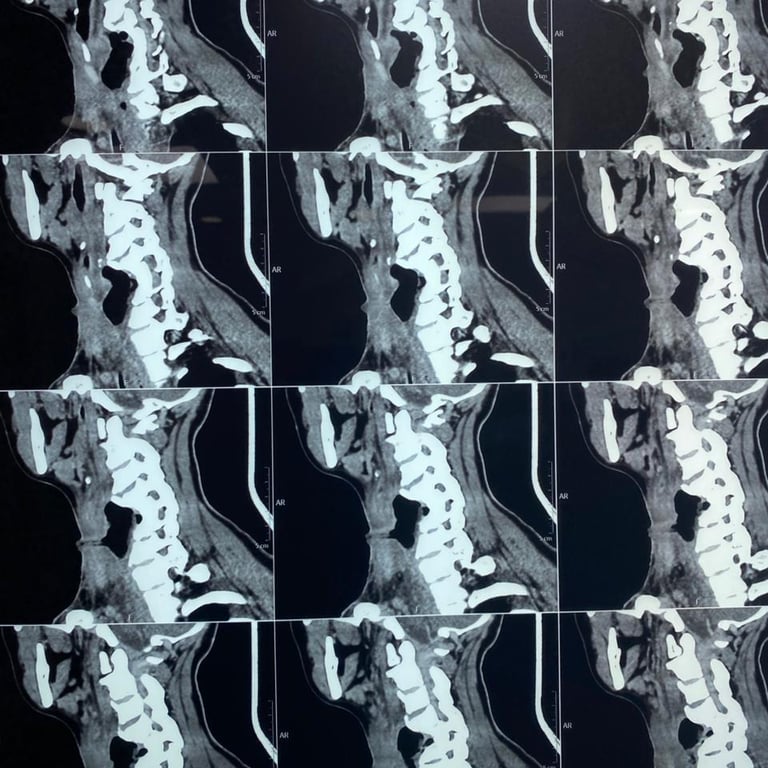

Upon presentation to me, a thorough clinical evaluation was performed, including endoscopic examination and imaging with CT and MRI.

In addition to confirming the chronic pharyngocutaneous fistula, imaging revealed a previously undetected large pharyngeal pouch, contributing to persistent leakage and impaired swallowing. Identifying this concealed pathology was critical to designing a definitive surgical strategy.